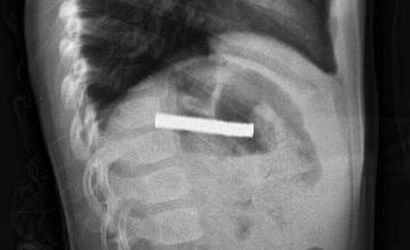

Erzurum'da evde oyun oynarken bulduğu 19 mıknatısı yutan 3 yaşındaki çocuk, rahatsızlanması üzerine ambulansla Erzurum Şehir Hastanesi'ne kaldırıldı. Yapılan tetkiklerin ardından hasta, acil durum nedeniyle ambulans helikopter ile Fırat Üniversitesi (FÜ) Hastanesi'ne sevk edildi.

FÜ Çocuk Gastroenteroloji Hepatoloji ve Beslenme Bilim Dalı Başkanı Prof. Dr. Yaşar Doğan ve ekibinin tetkiklerinde mıknatısların birbirine yapışarak çocuğun yemek borusunu tıkadığı tespit edildi. Müdahale sırasında mıknatıslar yemek borusundan mideye alınarak, mideden özel bir file ile çıkarıldı. İşlem başarılı geçti.

Elazığ'da 3 yaşındaki çocuğun yuttuğu ve yemek borusunu tıkayan 19 mıknatıs, Fırat Üniversitesi Hastanesi'nde yapılan başarılı bir operasyonla çıkarıldı.